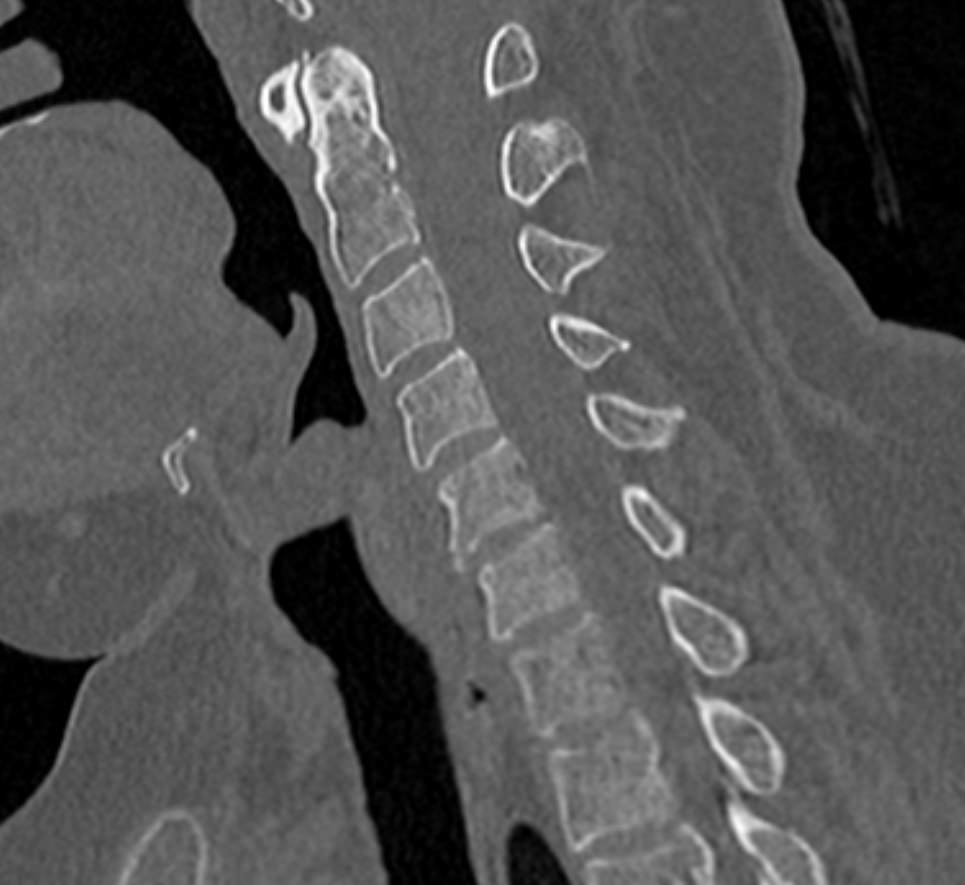

Мультиспиральная компьютерная томография (МСКТ) является современным, высокоинформативным методом диагностики различной патологии позвоночного столба. Благодаря МСКТ можно визуализировать костную структуру позвонков, выявить воспалительные, дегенеративные и опухолевые процессы на исследуемом уровне. В основе метода лежит использование ионизирующего излучения и способность различных тканей по-разному поглощать рентгеновские лучи.

В нашей клинике КТ двух отделов позвоночника проводится на новейших мультиспиральных томографах экспертного уровня TOSHIBA AQUILION (64-срезовый и 128-срезовый). Сканеры производят тончайшие срезы исследуемой зоны толщиной от 0,5 мм и позволяют визуализировать костные структуры позвоночника с высокой детализацией. Увеличенное количество высокочувствительных детекторов аппаратов обеспечивает высокую разрешающую способность и четкость изображений, при этом позволяет выполнить исследование в течение нескольких секунд с минимальной дозой облучения.

Инновационные возможности мультиспиральных томографов, которыми оснащены наши медицинские центры, позволяют создавать 3D-модели позвоночника на рассматриваемом уровне для более точной локализации очага и оценки взаимного расположения органов и тканей.